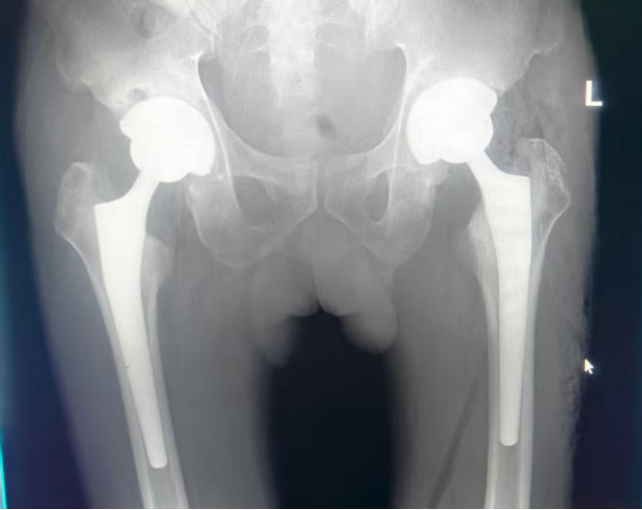

十一、验证作品

术中动态摄影。